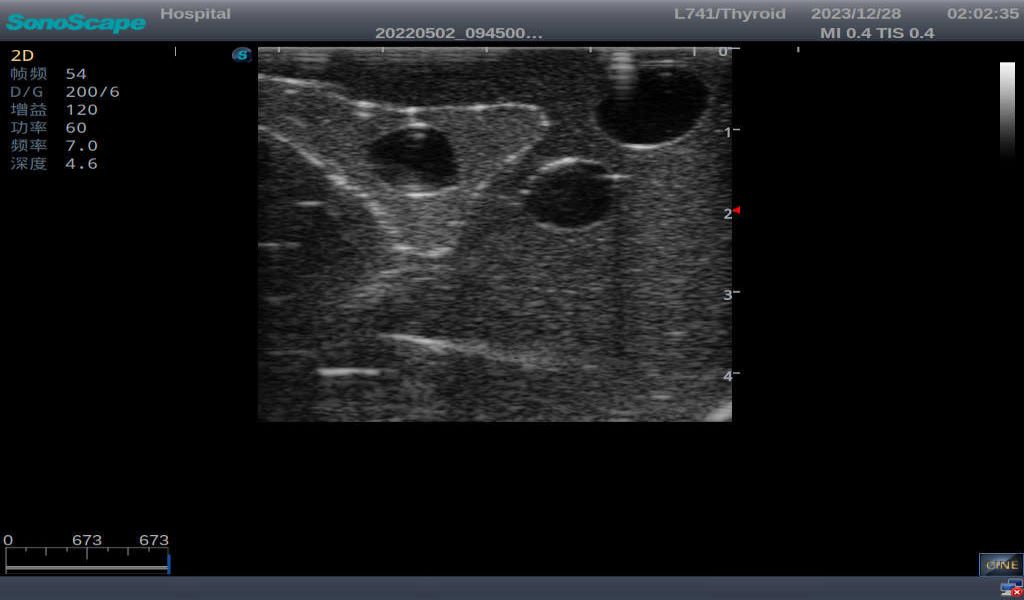

3)       It comes with four (4) thyroid modules and can show five (5) ultrasonic images: normal thyroid, thyroid adenoma, thyroid cancer, nodular goiter, thyroid cyst

Normal thyroid with homogeneous parenchymal echo and well-defined capsule

Thyroid cyst, which fluid area, dark and echo-free area can be seen